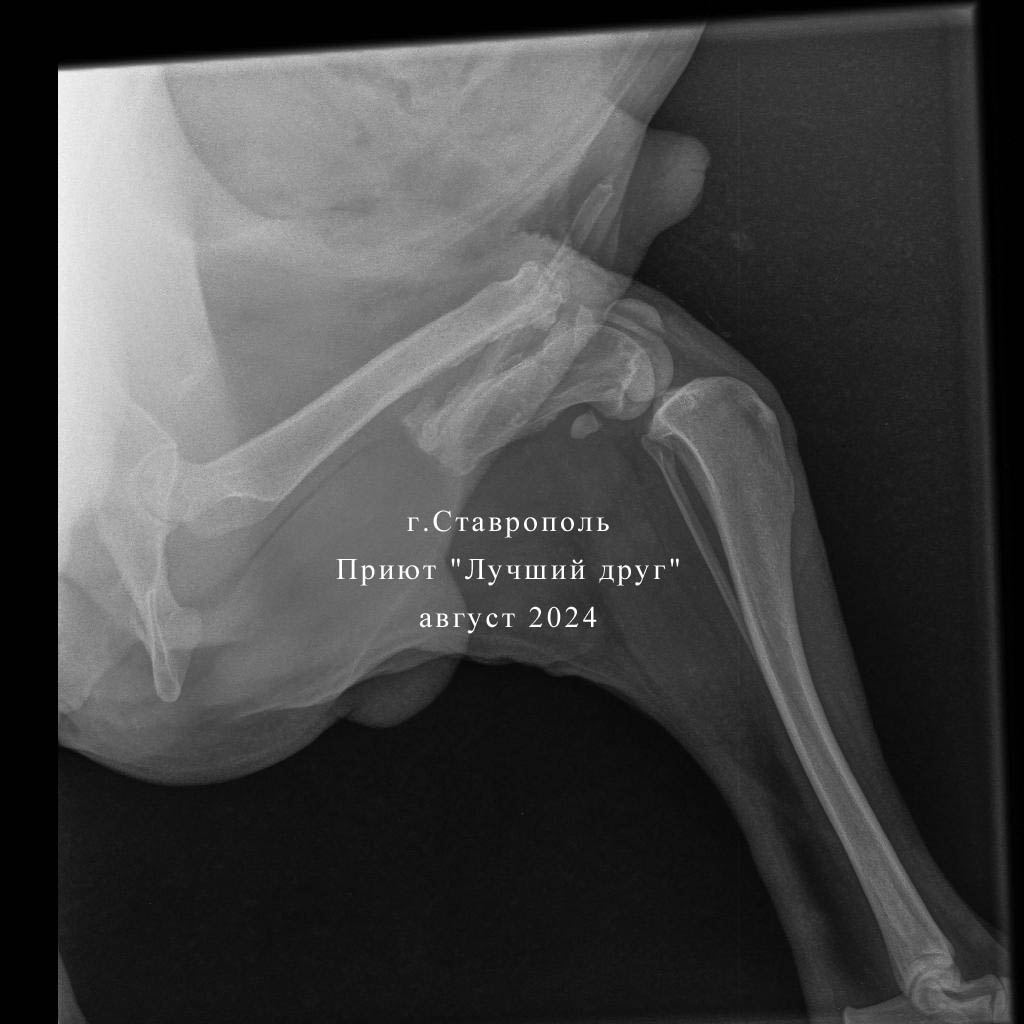

С большим трудом волонтеры привезли своенравного Мишаню в клинику, по рентгену у него перелом бедренной кости на левой тазовой конечности, сросшийся уже перелом правой задней лапы и пуля справа в подвздошной кости. Но это не так критично, как обнаруженное у пса новообразование предстательной железы. Взяли пункцию, там абсцесс, но вскрывать сейчас смысла нет. Стому не получился сделать из-за тяжелого состояния собаки. Если абсцесс вскрыть в брюшную полость, то получим по итогу спаечный процесс и перитонит. В любом случае, обширное операционное вмешательство пес не перенесет.